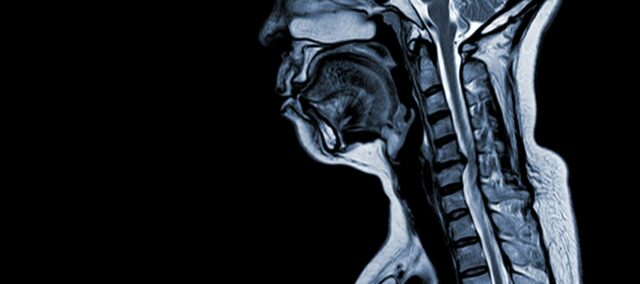

Servikal spondilotik miyelopati (CSM), yetişkinlerde omurilik hasarının önde gelen nedeni olan nörolojik bir durumdur. Basit bir ifadeyle, öncelikle boyun omurlarını etkileyen doğal yaşlanma sürecine bağlı olarak boyundaki omuriliğin sıkışması veya hasar görmesini içerir. 'Miyelopati' terimi Yunanca'da 'omurilik' anlamına gelen 'myelon' ve 'hastalık' anlamına gelen 'pathos' kelimelerinden gelmektedir.

CSM, servikal omurgadaki yapısal değişiklikleri içeren çok faktörlü bir patofizyolojiye sahip karmaşık bir tıbbi durumdur. Birkaç temel faktör gelişimine ve ilerlemesine katkıda bulunur:

- Disk Dejenerasyonu (Disk Bulging): CSM genellikle servikal omurgadaki intervertebral disklerin dejenerasyonu ile başlar ve omurilik kanalına doğru çıkıntı yapmalarına veya şişmelerine neden olur.

- Subperiosteal Kemik Oluşumu (Spinal Kanalın Ventralinde): Artan mekanik strese yanıt olarak vücut, omurilik kanalının ön (ventral) tarafında yeni kemik dokusu oluşturur ve potansiyel olarak omurilik için alanı daraltır.

- Posterior Longitudinal Ligament Ossifikasyonu: Posterior longitudinal ligament ossifikasyona uğrayabilir, sertleşebilir ve kalsifiye olarak spinal kanal daralmasına katkıda bulunabilir.

- Ligamentum Flavum Hipertrofisi: Ligamentum Flavum'un hipertrofisi kalınlaşmasına ve daha az esnek hale gelmesine neden olarak omurilik kanalı içindeki boşluğa daha fazla tecavüz eder ve omuriliği sıkıştırır.

Bu yapısal değişiklikler toplu olarak spinal kanalın sıkışmasına ve daralmasına yol açarak CSM ile ilişkili ayırt edici semptomlara ve komplikasyonlara neden olur. Bu risk faktörlerinin tanınması ve ilgili patofizyolojik mekanizmaların anlaşılması, hem önleme hem de yönetim için esastır. Erken tanı ve uygun müdahaleler, bu yapısal değişikliklerin omurilik üzerindeki etkilerini azaltmak için çok önemlidir.